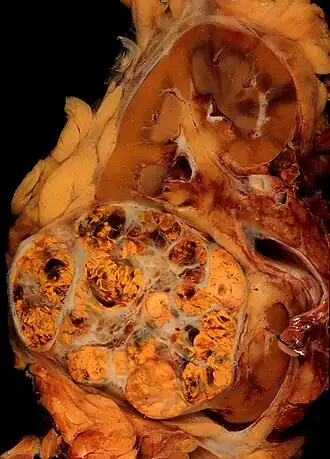

| Carcinoma de células renais (parte inferior mais laranja e branca) de 8cm, ultrapassando a cápsula renal. | |